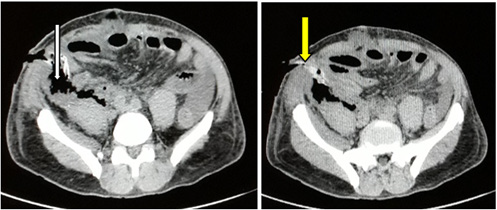

His collapse revealed a retroperitoneal, purulent and fecaloid effusion abundant as evidence of a posterior perforation of the right colon. We performed aspiration followed by retroperitoneal drainage. A sample of the pus was taken for bacteriological analysis. A trilateral ileocolonic shunt associated with drainage was performed as a first-line treatment due to the patient’s hemodynamic instability. Postoperatively, the patient was put on triple antibiotic therapy consisting of cefepime, metronidazole and gentamicin. High-protein oral feeding was allowed from the second day (D2) postoperatively. A follow-up thoraco-abdominal CT scan performed on D9 showed regression of the right retroperitoneal effusion (Figure 2) and bilateral pleurisy.

Figure 2: J9 abdominal CT scan, showing a retro pneumoperitoneum (white arrow) and the exteriorized drain (yellow arrow).